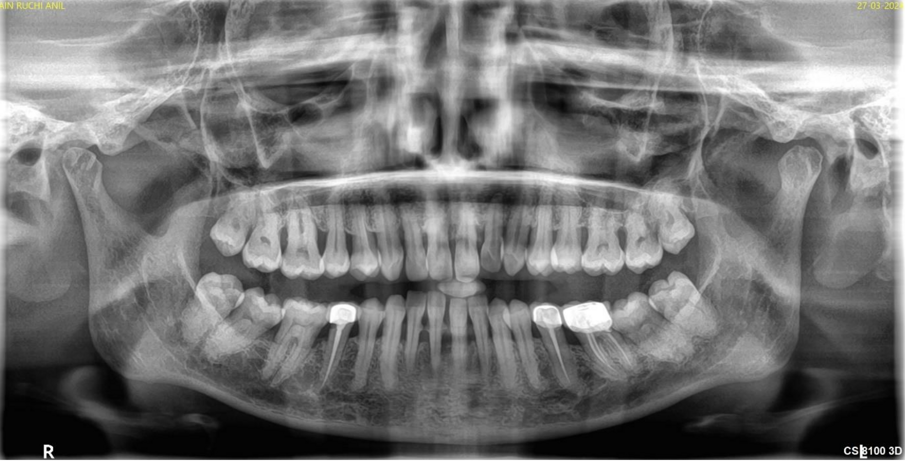

The critical stage of treatment planning is the determination of a tooth’s prognosis. There are several ways of helping with this decision-making – some quite elaborate and expansive taking into consideration both patient factors like willingness and finances and clinical factors like pocket depth, etc.1 Unfortunately, though we make decisions based on bone loss, pocket depth, mobility, etc., —the truth is that the same teeth with the same conditions existing in different patients will have a different prognosis based on hygiene, maintenance, follow-up, masticatory loads, and a certain degree of unpredictability brought in by a wide range of variables that exist at any given time in a patient’s mouth. A clinician’s expertise with regard to both diagnosis and treatment will also determine the success of either treatment. Therefore, following a set flowchart to decide the fate of a tooth is not enough—a clinician needs to bring acumen, experience, something close to intuition, and knowledge of that particular patient to the table. Consolidate all the data and then decide the best course of action.

Even so-called hopeless teeth have been preserved successfully with adequate periodontal treatment followed by strict supportive periodontal treatment (SPT).2,3 Patients with treated aggressive periodontitis have also shown survival of teeth as long as 15 years after treatment.4 This means that patients with seemingly hopeless dentition too could be given the option of holding on to their teeth. They need to be informed that it will just come with a caveat that they must take responsibility for their condition and strictly follow the dentist’s treatment plan and maintenance protocol. At such a time we need to refrain from glamorising the alternative option of an implant—falsely presenting it in a way that suggests that it does not need as much care or that it would last forever. It holds to reason if presented in such a manner 100% of patients who could afford implants, would opt for implants. As soon as an implant is presented as an option it creates a bias in treatment planning as well.5 An implant success rate of 98% and above is misleading as that only refers to its survival in the mouth and not a peri-implant disease, inflammation, or bone loss that afflicts a great number of those surviving implants.6 Therefore, it becomes imperative to present dental implants in a responsible ethical manner—explaining the benefits but also the fact that it is not a fill-it-and-forget-it-situation.

For all patients who opt to save their teeth—the maintenance phase is not just important for the survival of teeth—it is also to ensure no deterioration to a point where it would compromise or jeopardize future implant treatment. We have often in our experience found patients stable for four to six years with regular SPT and suddenly be lost to recall until they turn up ten years later where we are left with no bone to place implants in a conventional manner then resorting to extreme bone augmentation or zygomatic and pterygoid implants. Hence the delicate balance of when saving teeth versus extracting and implants needs to be revisited regularly in each patient to ensure that maintenance of the teeth is not risking the loss of residual bone.